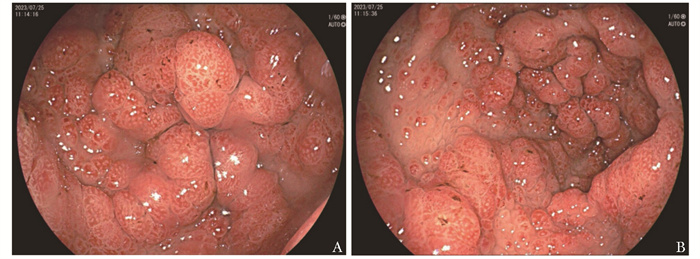

• 摘要: 本文报道Cronkhite-Canada综合征合并无症状新型冠状病毒感染1例。该患者临床表现为食欲减退,毛发及指甲脱落,皮肤色素沉着。内镜检查见胃、十二指肠及结肠黏膜呈弥漫性、大小不一、密集分布的息肉样改变。病程中检出新型冠状病毒核酸阳性。经中等剂量泼尼松治疗后,患者毛发恢复生长,皮肤色素沉着减退。本文总结该患者的诊疗经过并结合文献复习,以期提升临床医生对该病的认知。

Abstract: This article presents a case study of a patient who had Cronkhite-Canada syndrome in combination with an asymptomatic novel coronavirus infection. The patient exhibited clinical symptoms of loss of appetite, hair and nail loss, and skin pigmentation. Digestive endoscopy revealed widespread and varying-sized polypoid changes in the mucosa of the stomach, duodenum, and colon. During the course of the illness, the patient tested positive for novel coronavirus nucleic acid. Treatment with moderate doses of prednisone resulted in the patient's hair regrowth and decreased skin hypopigmentation. The article provides a summary of the patient's diagnosis and treatment and a review of relevant literature, with the aim of enhancing clinicians' understanding of the disease.